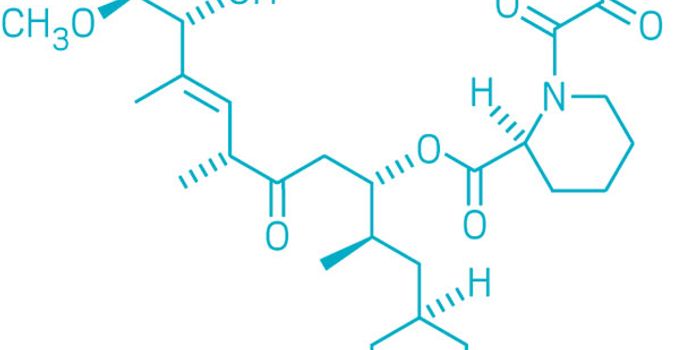

MAY 23, 2019Drug Discovery & DevelopmentRapamycin was considered a wonder drug upon its discovery three decades ago when it was isolated from soil bacteria. It ...